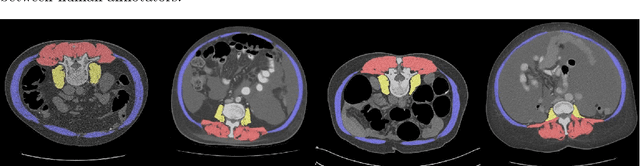

Abstract:Objective: To demonstrate the effectiveness of using a deep learning-based approach for a fully automated slice-based measurement of muscle mass for assessing sarcopenia on CT scans of the abdomen without any case exclusion criteria. Materials and Methods: This retrospective study was conducted using a collection of public and privately available CT images (n = 1070). The method consisted of two stages: slice detection from a CT volume and single-slice CT segmentation. Both stages used Fully Convolutional Neural Networks (FCNN) and were based on a UNet-like architecture. Input data consisted of CT volumes with a variety of fields of view. The output consisted of a segmented muscle mass on a CT slice at the level of L3 vertebra. The muscle mass is segmented into erector spinae, psoas, and rectus abdominus muscle groups. The output was tested against manual ground-truth segmentation by an expert annotator. Results: 3-fold cross validation was used to evaluate the proposed method. The slice detection cross validation error was 1.41+-5.02 (in slices). The segmentation cross validation Dice overlaps were 0.97+-0.02, 0.95+-0.04, 0.94+-0.04 for erector spinae, psoas, and rectus abdominus, respectively, and 0.96+-0.02 for the combined muscle mass. Conclusion: A deep learning approach to detect CT slices and segment muscle mass to perform slice-based analysis of sarcopenia is an effective and promising approach. The use of FCNN to accurately and efficiently detect a slice in CT volumes with a variety of fields of view, occlusions, and slice thicknesses was demonstrated.